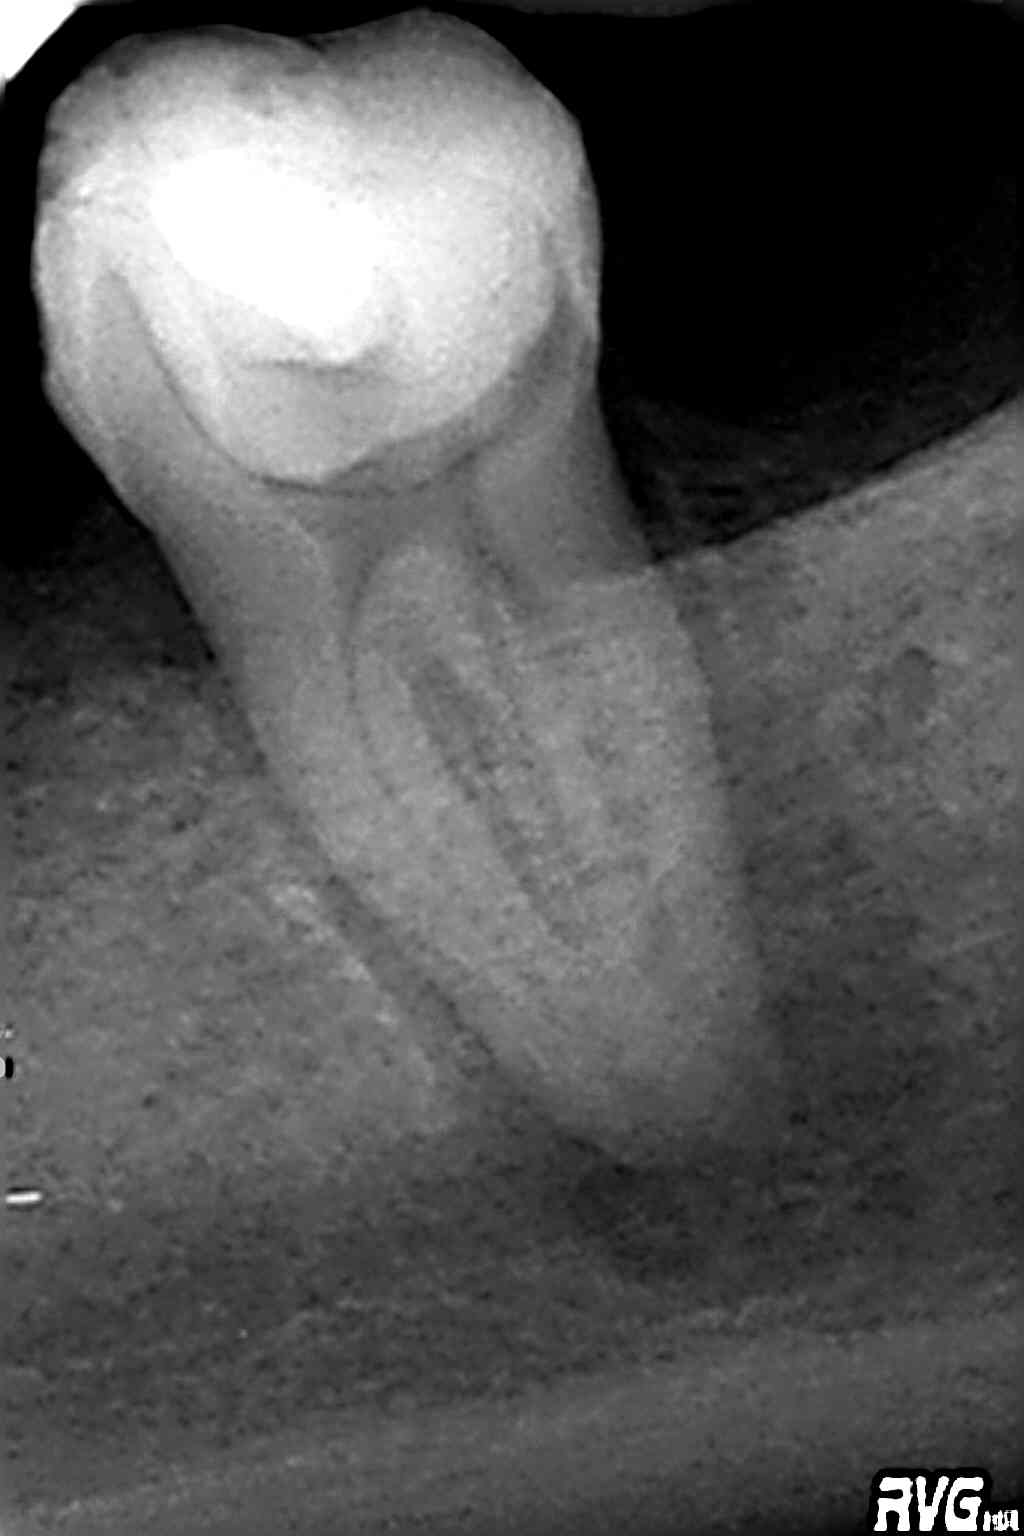

Llega a nuestra consulta una pieza 3.7 con una lesión periapical, se le realiza un tratamiento de conductos.

Se instrumenta con un sistema de limas Protaper unida a una irrigación profusa ayudado de la punta de ultrasonidos Irrisafe, se obturó con técnica híbrida, condensación vertical más gutapercha inyectada.

El paciente vino a la revisión de dicha pieza a los 9 meses, según el paciente no tenía síntomas y la lesión había regenerado.